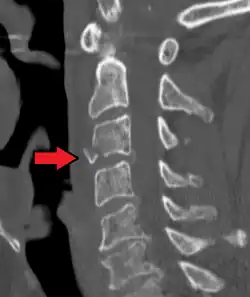

A fracture of the base of the dens (a part of C2) as seen on CT